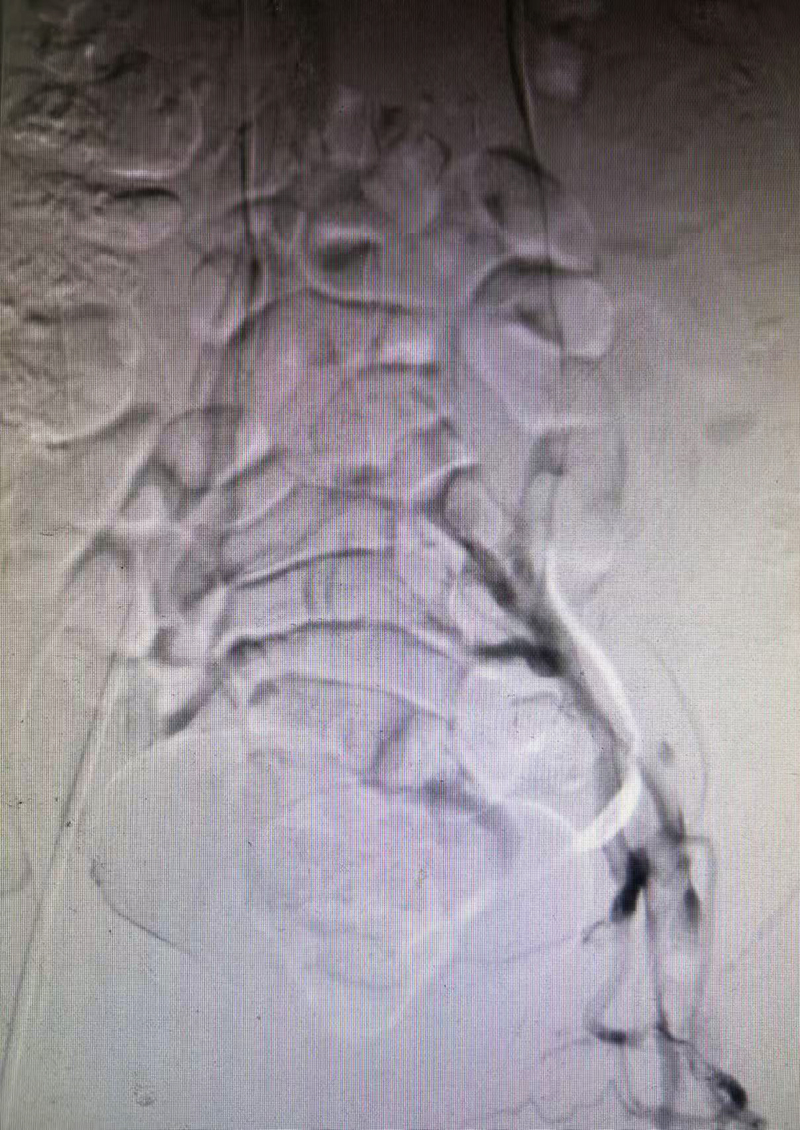

1.肺动脉介入溶栓——打通“生命通道”:术中造影显示患者右肺动脉主干及分支血流明显受阻,术者经导管持续泵入溶栓药物,直接作用于血栓内部,实现“精准打击”,卢女士即刻感到胸闷、胸痛症状明显缓解。

2.髂股静脉血栓减容——清除“罪魁祸首”:肺动脉危机解除后,术者将注意力转向下肢静脉血栓的源头。造影可见左侧髂股静脉血管几近闭塞,采用机械血栓抽吸装置在负压吸引下将大量新鲜血栓逐段清除,并进行球囊扩张,进一步碎裂残留血栓并恢复管腔通畅。术中抽出暗红色血栓约80毫升,患者左下肢的肿胀即刻缓解。